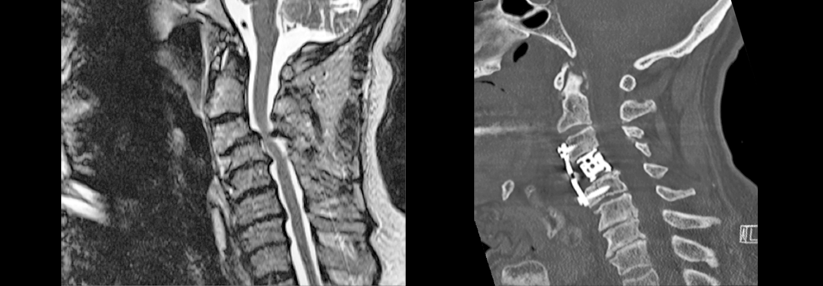

Die bildgebende Diagnostik sollte mit einer seitlichen Funktionsaufnahme in Inklination starten. Beträgt die atlantodentale Distanz mehr als 5 mm, muss man von einer Zerstörung der Bänder ausgehen. Diese erfordert eine a.p.-Aufnahme sowie je eine laterale Aufnahme in Reklination und Neutralposition. Bei fraglicher OP-Indikation schließt sich eine MRT an. Um das Ausmaß knöcherner Destruktionen zu beurteilen, eignet sich eine CT am besten. Myelonschäden lassen sich am ehesten über evozierte Potenzialmessungen aufdecken.